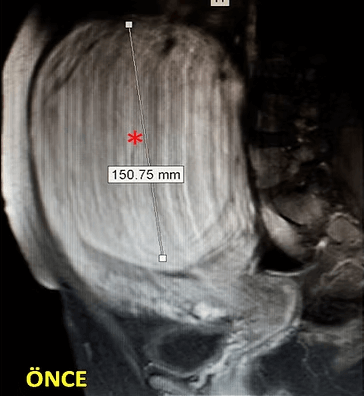

41 yaşında, kabızlık, gaz ve sık idrara çıkma şikayetleri var. Emar’da karını dolduran dev miyom (*) mevcut. Miyomektomi önerilmiş, ancak operasyonda rahimin alınabileceği söylenmiş. Embolizasyondan sonra dev miyomun ve bir başka küçük miyomun öldüğü ve küçüldüğü izleniyor. 7 ay sonra hasta şikayeti kalmamıştır.